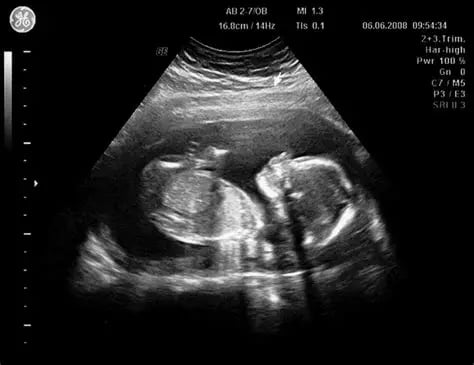

Ecografías

En IPS Santa Salud, Aguachica, Cesar, ofrecemos servicios de ecografía con tecnología de última generación, garantizando imágenes claras y diagnósticos precisos. Nuestro equipo de especialistas está capacitado para brindar una atención cercana y confiable, cuidando tu bienestar y el de tu familia.

Realizamos estudios ecográficos para diferentes necesidades médicas, asegurando resultados rápidos y confiables que apoyan tu salud integral.